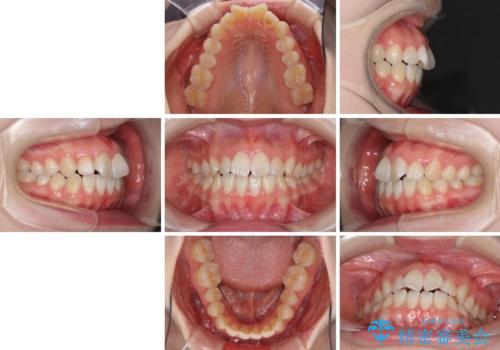

- 前歯の捻れと、ちょっとした出っ張りを気にして来院された患者様です。

歯と歯の間を削る(IPR)ことでデコボコを解消し、インビザラインで整えることとしました。

インビザライン治療特有の奥歯が接触しない時期が続き、当初予定よりも期間がかかりましたが、最終的には安定した咬み合わせと、整った前歯になりました。